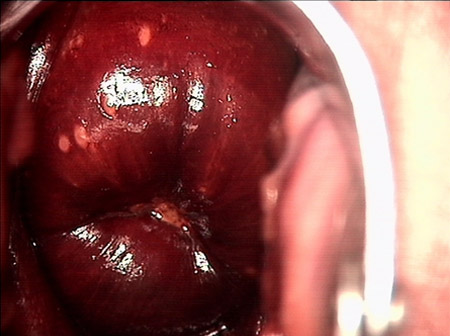

婦科leep錐切手術(shù) CIN2-3

• CIN 2-3CIN 2-3